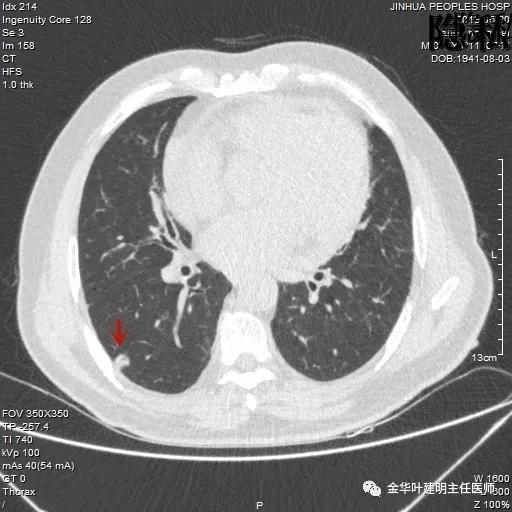

以上是2018年5月的片子,此处也呈空腔性病灶,但也点像是个肺大泡,因为绿色箭头所指处也有肺大泡。